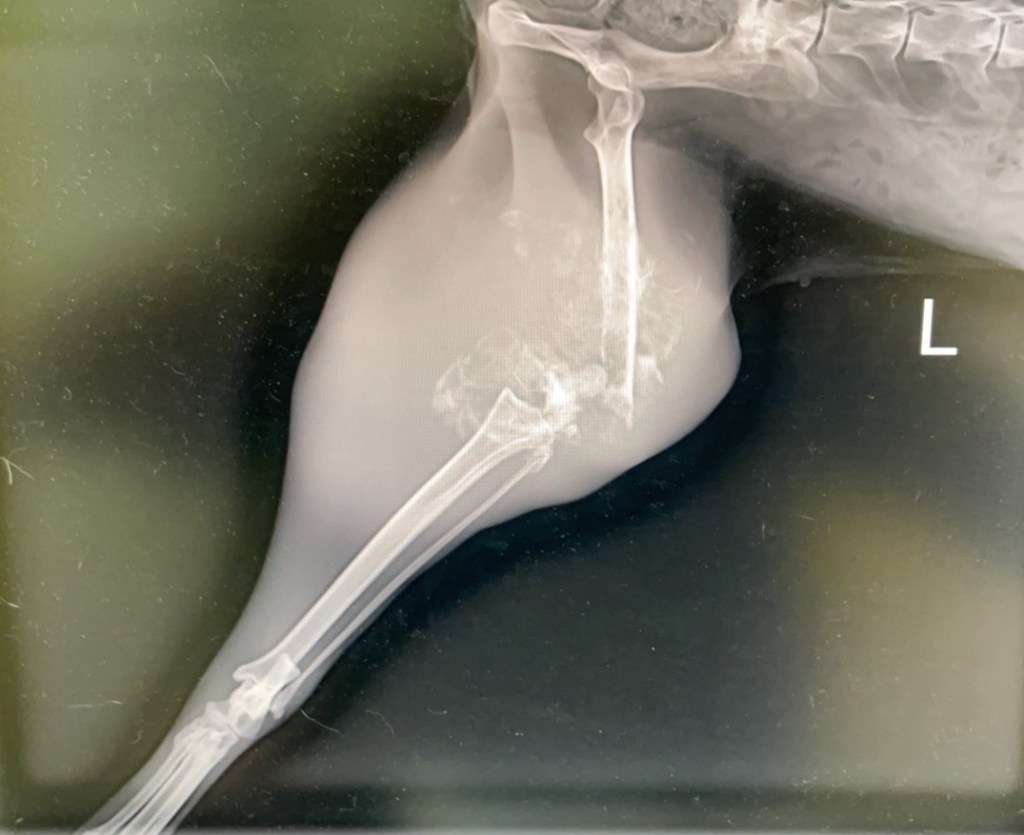

『骨肉瘤』常見症狀,從跛腳、腫起開始,必須透過X光才能確診。

『骨肉瘤』臨床症狀,通常從跛腳,腫起開始,然後骨頭疼痛、食慾下降、局部腫脹,而且運動量逐漸變少。這種症狀屬於惡性骨癌,會不斷的侵略附近的骨頭,造成骨質被掏空、骨頭空虛…;嚴重時,骨頭因此而變得脆弱,進而產生骨頭的病理性骨折。這時候,必須透過X光觀察骨頭的變化,觀察骨頭腐蝕、被溶解…,此時幾乎就可以確診,是罹患『骨肉瘤』無誤。

帶到『啄木鳥動物醫院』X光檢查、病理採樣,確定是『骨肉瘤』。

九歲大的小咪,就是不幸罹患『骨肉瘤』的案例!大約三個月前,主人發現小咪的後腿腫起,初期只當作是外傷撞擊引起的腫脹,並不太在意;不料左後腿(大腿骨)越腫越大,變得無法正常走路,這才帶到台南『啄木鳥動物醫院』看診,啄木鳥立刻用X光檢查,再做病理採樣分析,確診是可怕的『骨肉瘤』無誤,由於『骨肉瘤』轉移肝臟、肺臟、全身的機率很高,只好毅然決定截肢。